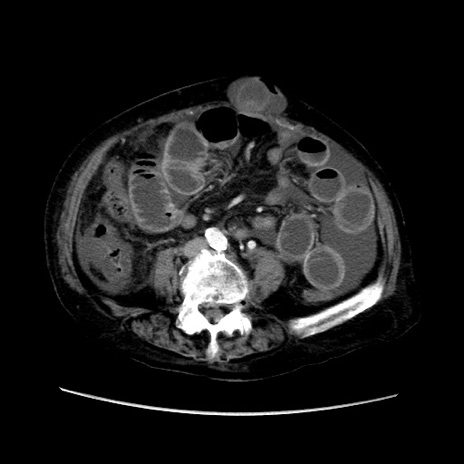

症例31(横断像)

【症例】80歳代 女性

【主訴】腹部膨満感

【現病歴】他院にて肝硬変にてフォロー中。1週間前から便秘、腹部膨満感、臍部腫瘤あり受診となる。

【既往歴】肝硬変

【身体所見】腹部膨隆あり、皮膚変化なし、疼痛なし。

【データ】WBC 4600、CRP 0.25